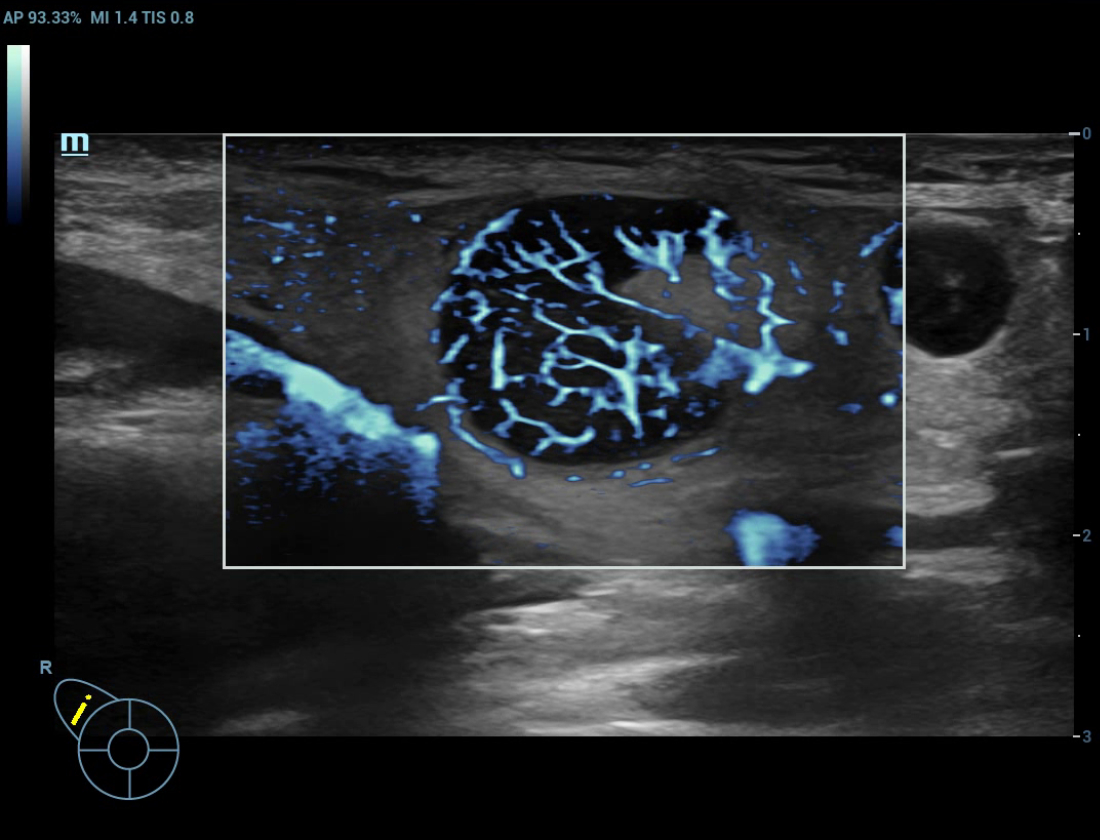

Ultra Micro Angiography (UMA)

UMA migliora la sicurezza diagnostica ampliando la visibilitĂ dei flussi sanguigni fino al livello dei vasi piĂč piccoli, con una sensibilitĂ e una risoluzione superiori.

Massa mammaria pUMA

CEUS UWN+(Ultra-Wideband Non-linear)

CEUS tumore maligno al seno

Utilizzando sia i segnali fondamentali di seconda armonica che quelli non lineari, UWN+ consente un'elevata sensibilitĂ ai segnali delle microbolle e una perfusione di contrasto piĂč lunga con un MI piĂč basso, per contribuire alla valutazione dei tumori.

Massa mammaria cUMA

Massa mammaria

Massa mammaria CEUS